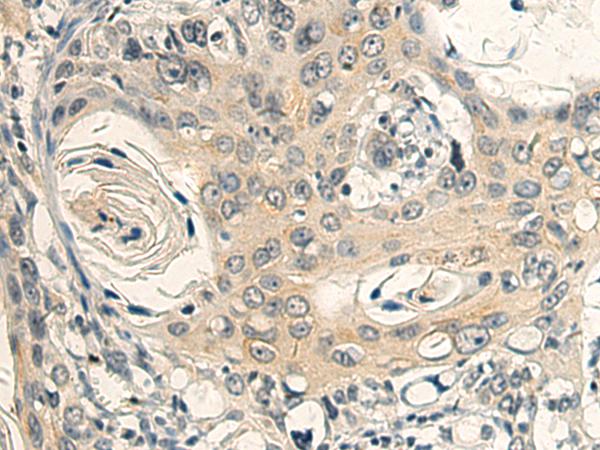

IHC positive control:

Human esophagus cancer and Human colorectal cancer

ELISA, IHC